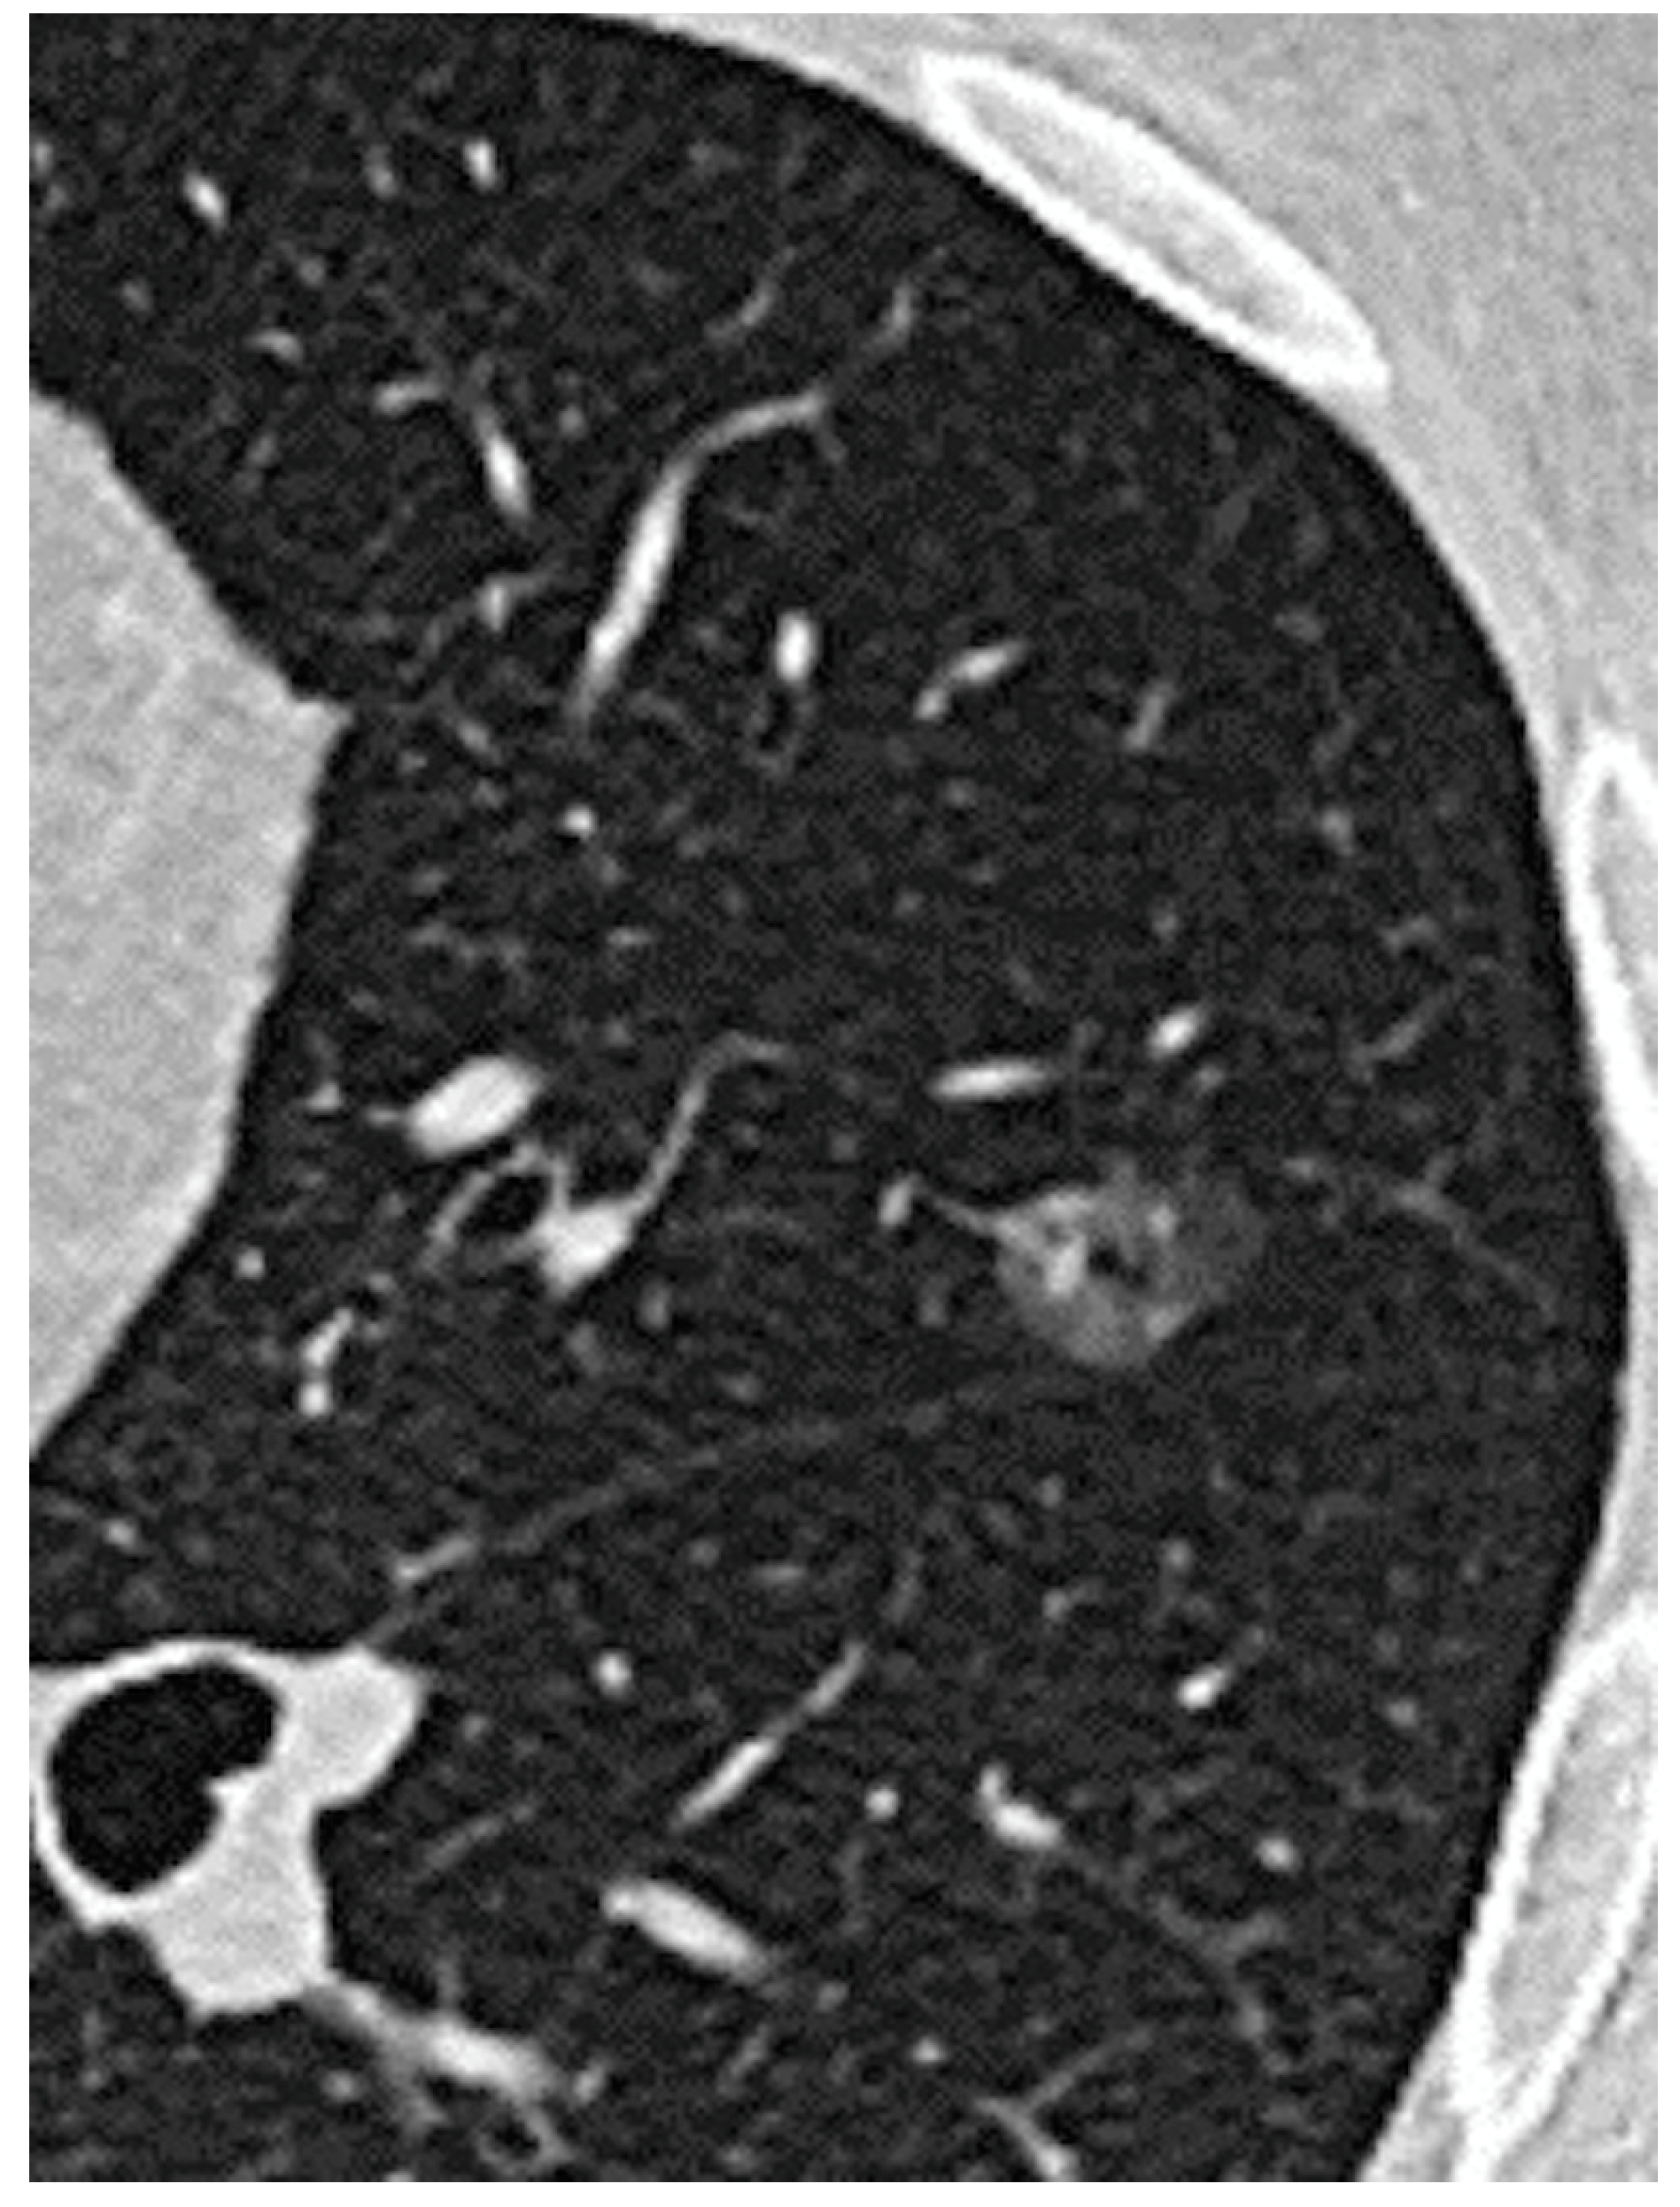

Prognostic Factors of Non-Predominant-Lepidic Lung Adenocarcinoma Presenting as Ground Glass Opacity: Results of a Multicenter Study

| Pure GGO, n (%) | 162 (42%) | 108 (67%) | 54 (24%) | <0.0001 |